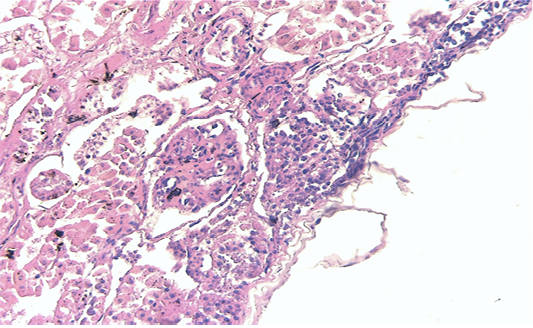

Kidney showing large multifocal areas of coagulative necrosis, associated with marked marginal hyperemia, interstitial nephritis, with presence of mononuclear and polymorphonuclear cells (H & E × 40, bar 100 μm).